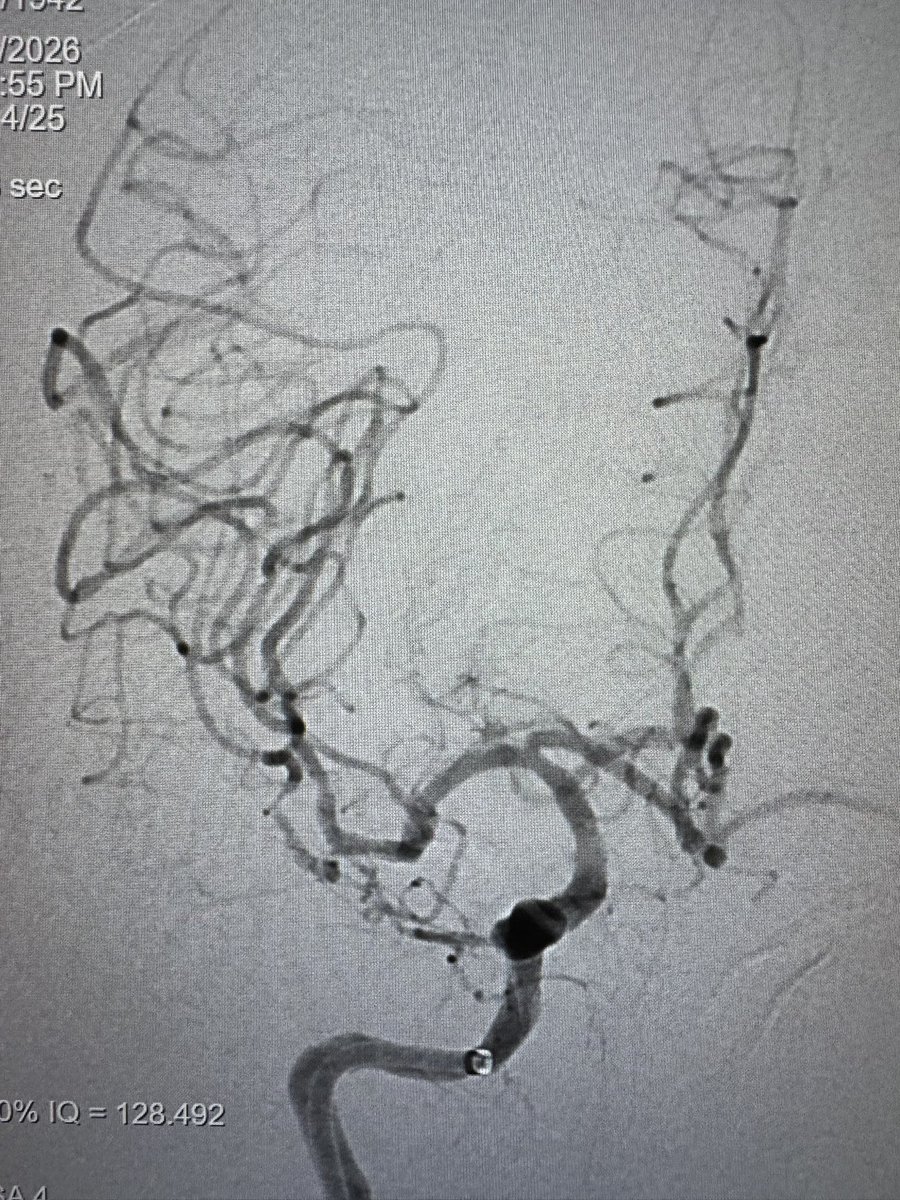

اليوم اجتزت حد الخمس الاف حاله تداخليه عصبيه قدمت فيها علاجات تداخليه عاجله ومجدوله للأمراض الوعائيه في الدماغ والحبل الشوكي وكذلك علاج الأورام التداخلي والعلاج المزمن للالم

حاله اليوم كانت سحب جلطه دماغيه حاده تكللت بالنجاح ولله الحمد

تجربه جميله تعلمت منها الكثير ودفعتني مقومات العمل والنظم الصحيه إلى تفعيل وابتكار عدد من طرق العلاج لتحقيق الفائده الكبرى للمرضى

سحب وعوده thrombectomy and back (مبتكر)

انطلاق وسحب drive and retrieve (مبتكر)

وكذلك أسلوب علاج مبتكر لأم الدم coil and go يضمن علاج المريض في وقت قياسي متجاوزين عقبات انتقال المرضى بين المستشفيات والحمايه من معاوده النزيف الدماغيه